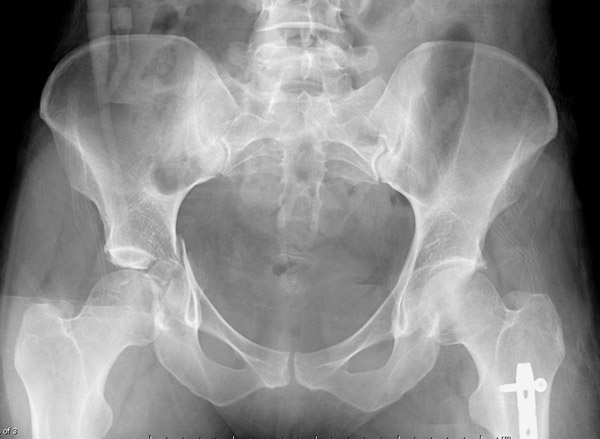

Пациент 19 лет, ДТП в сентябре 2012 г, оперирован поэтапно в др. клинике. В сентябре пациенту первым этапом была проведена операция – МОС лодыжек правой голени, МОС правой бедренной кости. Через 2 недели была проведена операция МОС костей таза и открытое устранение вывиха правого бедра.

Повторная операция – реостеосинтез костей таза была проведена через 1 месяц после первичной. Дз: задний вывих правого бедра (сроки -3 месяца). Асептический некроз головки правой бедренной кости. Неконсолидирующийся перелом средней трети правой бедренной кости, неправильно консолидирующийся перелом лодыжек правой голени с подвывихом стопы кзади, передняя медиальная нестабильность правого К/С. Сгибательно-приводящая контрактура правого Т/Б сустава, сгибательно-разгибательная контрактура правого К/С, эквинусная установка в правой стопе на фоне пост-операционного пареза

Перелом вертлужной впадины отличается от “переломов таза” не только исследованием, но также тактикой. По классификации Летурнеля расположение линии перелома характерно для поперечного перелома вертлужной впадины, но наличие шурупов в заднем крае (второй снимок) и вывих бедра подтверждают, что здесь сочетание заднего края с поперечным переломом.

Надо сделать снимки Judet и при возможности КТ. А 3Д снимки покажут общий вид, но детали в области суставов дает срезы КТ.